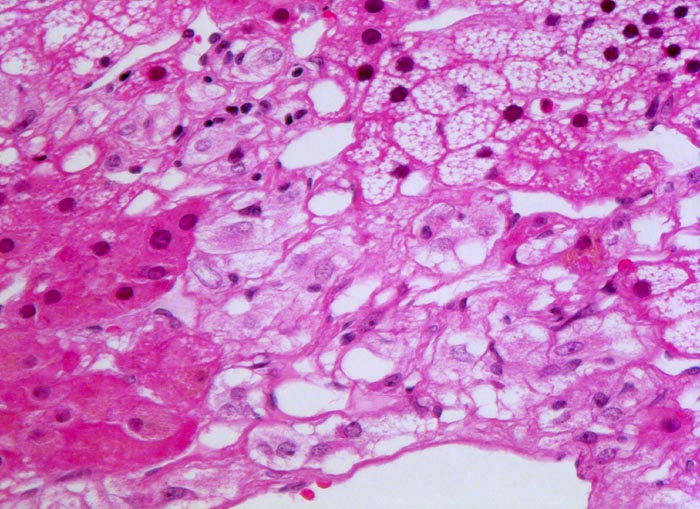

Phaeochromozytom

Nebenniere

Basophile Tumorzellen, welche an normales Nebennierenmark erinnern infiltrieren die Zona fasciculata ( lipidreiche Zellen mit vakuolisiertem Zytoplasma) und die Zona reticularis ( lipofuscinhaltige Zellen).

Der Patient klagt über rezidivierende Kopfschmerzen seit zirka zwei Monaten. In letzter Zeit hat er Alcacyl genommen, jedoch ohne Erfolg. Die Computertomographie des Abdomens zeigt einen 5cm grossen Tumor im Bereich der rechten Nebenniere. Die Familienanamnese für multiple endokrine Neoplasien (MEN) ist bland.

320